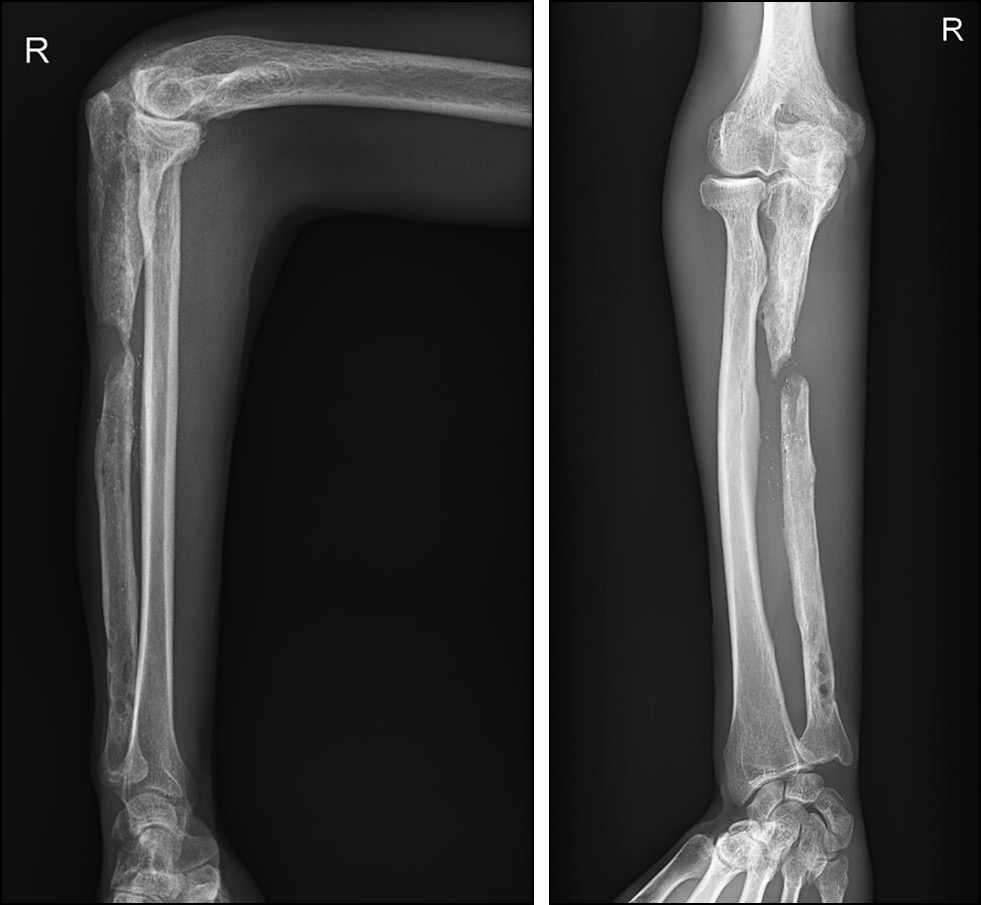

Пациент Р., 42 года, поступил в травматолого-ортопедическое отделение ГАУЗ СО «Свердловский областной клинический психоневрологический госпиталь для ветеранов войн» с жалобами на боль в правом предплечье, выраженное ограничение движений в правом локтевом и лучезапястном суставе, нарушение функции правой верхней конечности. Из анамнеза выяснено, что в 2019 году получена производственная травма. По этому поводу был выполнен закрытый интрамедуллярный блокируемый остеосинтез перелома правой локтевой кости стержнем. Спустя 6 месяцев — излом стержня, псевдоартроз правой локтевой кости в верхней трети диафиза. Выполнены удаление стержня, реостеосинтез локтевой кости пластиной. Спустя 2 недели в верхней трети правого предплечья открылся свищ с гнойным отделяемым. Пациент взят на хирургическую обработку, санацию, выполнено удаление пластины. Конечность фиксирована косыночной повязкой. Данных о бактериальных посевах содержимого раны нет. Признаков инфекции в последующем периоде не наблюдалось. Через 1 год в ином областном учреждении пациенту выполнен остеосинтез правой локтевой кости пластиной с костной аутопластикой трикортикально-губчатым трансплантатом из гребня подвздошной кости. На контрольных рентгенограммах спустя 2 месяца выявлен лизис трансплантата. Жалобы пациента на боли в правом предплечье. Со слов пациента, однократно открывался свищ без содержимого в области оперативного вмешательства, он самостоятельно выполнял перевязки, после чего свищ закрылся. Выполнена повторная операция — удаление пластины из правой локтевой кости, санация, хирургическая обработка, остеосинтез правой локтевой кости аппаратом Илизарова. Спустя 2 месяца — параспицевая инфекция, обострение свищевой формы остеомиелита правого предплечья. Поступил в гнойное отделение Госпиталя для ветеранов войн. Выполнены демонтаж аппарата Илизарова, повторная санация, хирургическая обработка и дренирование. Правая верхняя конечность фиксирована косыночной повязкой. По результатам цитологического и бактериологического исследования раневого содержимого данных об инфекционном процессе не получено. Через 4 месяца обратился в травматолого-ортопедическое отделение Госпиталя для ветеранов войн с диагнозом «дефект-псевдоартроз верхней трети диафиза правой локтевой кости. Хронический посттравматический остеомиелит правой локтевой кости, свищевая форма, ремиссия». Объективно ось правой верхней конечности отклонена за счёт деформации в верхней трети правого предплечья, укорочение правого предплечья составило 2 см (D <S). Активные движения в локтевом суставе ограничены: сгибание — до 100°, разгибание — 130°, ротация предплечья — 5–0–10°. Активные движения в правом лучезапястном суставе ограничены: сгибание — до 15°, разгибание — 0°, отведение и приведение — в минимальной амплитуде. При движениях испытывает умеренную боль. Болезненность при пальпации, пальпаторно определяется дефект до 2 см в верхней трети правой локтевой кости. Крепитации отломков нет. Послеоперационные рубцы от аппарата Илизарова и предыдущих операций по разгибательной поверхности предплечья длиной до 20 см, нормотрофический рубец, безболезненный. Свищ в области хирургических вмешательств эпителизировался. Периферических сосудистых и неврологических расстройств нет. Функциональная оценка по шкале Disability of the Arm, Shoulder and Hand Outcome Measure (DASH) — 76 баллов. По рентгенограммам определяется костный дефект-псевдоартроз верхней трети диафиза правой локтевой кости (рис. 1). Диастаз между отломками локтевой кости до 30 мм.

Рис. 1. Рентгенограммы правого предплечья в двух проекциях.

Fig. 1. Radiographs of the right forearm in two projections .